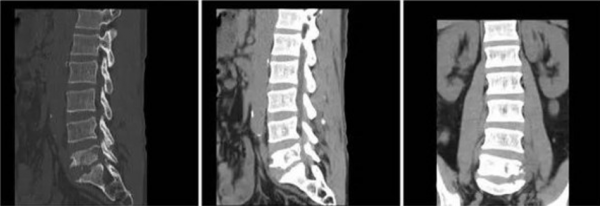

“第二板斧”,就是我們螺旋CT腰椎三維檢查(如圖2)。一聽名字,便能很好理解它的特點。CT是一種三維影象掃描,不僅可以立體化、詳細化觀察骨質情況,還可以粗略檢查椎間盤及周圍軟組織的情況。

當然,CT檢查也必定伴有輻射,它比X線劑量要更高一些。